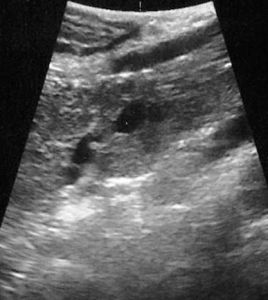

image

Lesione non visibile all’imaging TC e RM. All’ecografia intraoperatoria si rileva millimetrica nodulazione isoecogena in regione istmica determinante stop del dotto pancreatico principale, dilatato a monte.